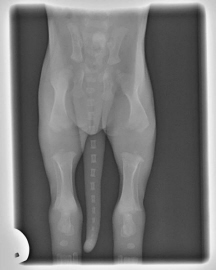

Puppy X-ray

Do not over exercise your pup.